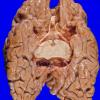

Neuronal Ceroid Lipofuscinosis (NCL) (6)